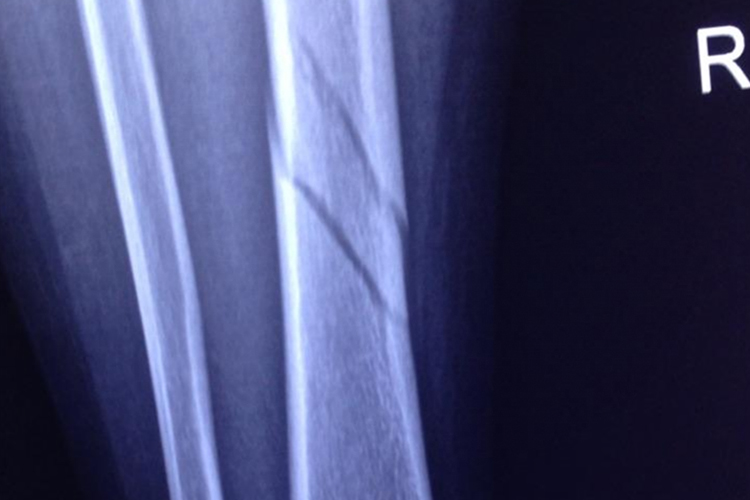

小腿骨折一般指的是胫腓骨骨折,临床常见骨折部位的疼痛、肿胀、畸形。

小腿骨折的主要症状是疼痛、肿胀、畸形和功能障碍。骨折后患肢有剧烈疼痛,尤以活动时加剧。对于儿童症状较轻的骨折、成人的单纯腓骨骨折,局部肿胀、压痛程度相对较轻,活动受限不明显,甚至可以行走。如骨折有明显的移位,可表现为小腿的畸形、反常活动,有骨擦音、骨擦感。